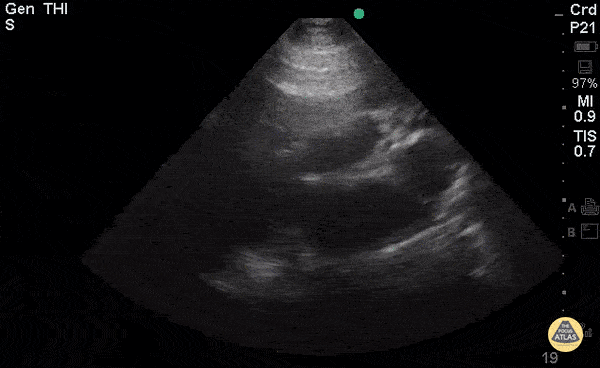

Right Ventricular Dysfunction - Right-Sided Heart Failure (PLAX)

Young woman with a history of Idiopathic Pulmonary Arterial Hypertension with resultant R heart failure who came in short of breath. Greg Powell, MD